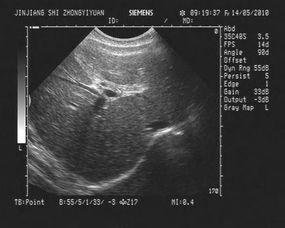

首先,让我们来了解一下“肝及虫视频”究竟是什么。据我了解,这类视频主要是一些关于肝脏健康和寄生虫防治的内容。它们通过生动形象的动画、图片和文字,向观众普及肝脏疾病和寄生虫感染的相关知识。